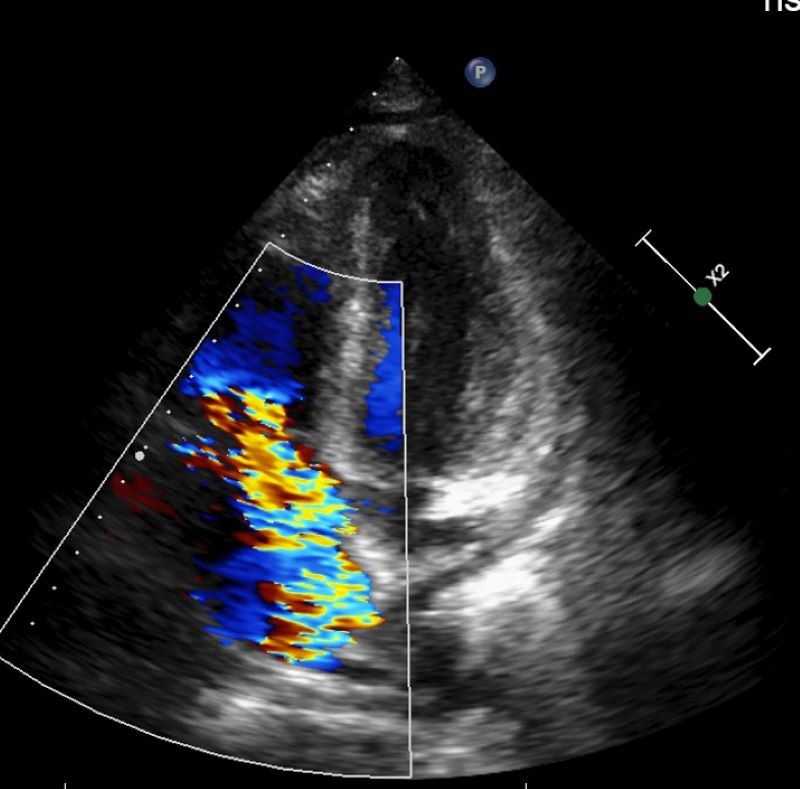

63歲的林先生去年底開始出現不明原因的反覆高燒,多次奔波診所求診始終找不到原因,後至醫院感染科就醫。抽血檢查顯示白血球、血小板及血紅素低下,必須輸血,但血液及骨髓等相關檢查均找不到病因,僅電腦斷層意外發現脾臟腫大與腹水。最後在住院的心臟超音波檢查中發現林先生罹患三尖瓣重度閉鎖不全,瓣膜上還長了一公分大的贅生物(即細菌感染的病灶),確診為感染性心內膜炎。會診心臟血管外科後更換人工生物瓣膜、同步清除感染病灶。病人血球數值明顯回升,順利恢復健康。

楊凱文指出,三尖瓣逆流並不少見,國外統計指出,有高達70%-80%的健康人群可見輕微三尖瓣逆流;但中重度以上的三尖瓣逆流發生率則較低,約占整體人口的1%-2%。大多數患者初期多無明顯症狀,直至中重度以上才會有輕微水腫出現,因此許多人往往會忽略其嚴重性,待出現嚴重問題時多已經變成重度逆流。他說,三尖瓣逆流大多可以用藥物控制,若是進展為重度逆流且藥物治療效果不彰,同時合併右心室功能異常,就會需要手術,但臨床案例不多。診斷上會以超音波檢查為主,手術則會視病人狀況選擇開胸或微創手術。